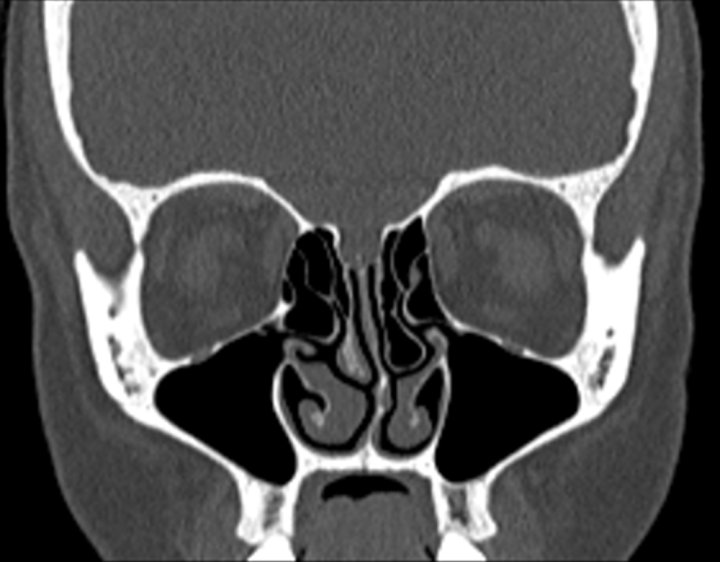

Click any image for labels.